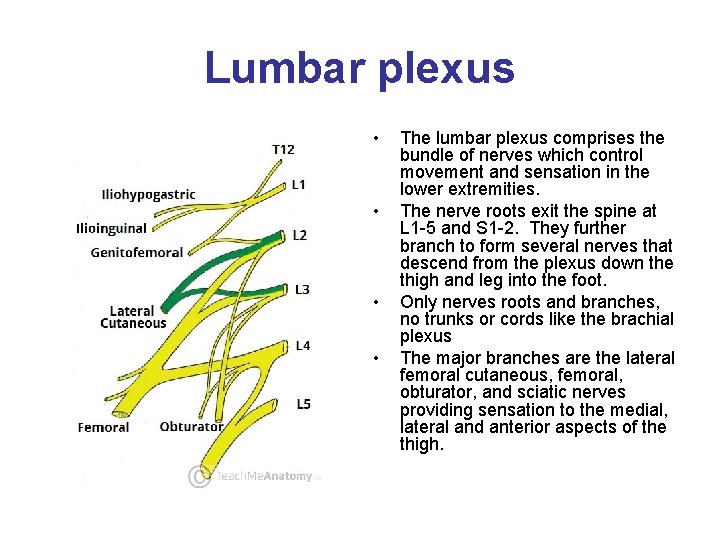

Lumbar plexus • • The lumbar plexus comprises the bundle of nerves which control movement and sensation in the lower extremities. The nerve roots exit the spine at L 1 -5 and S 1 -2. They further branch to form several nerves that descend from the plexus down the thigh and leg into the foot. Only nerves roots and branches, no trunks or cords like the brachial plexus The major branches are the lateral femoral cutaneous, femoral, obturator, and sciatic nerves providing sensation to the medial, lateral and anterior aspects of the thigh.